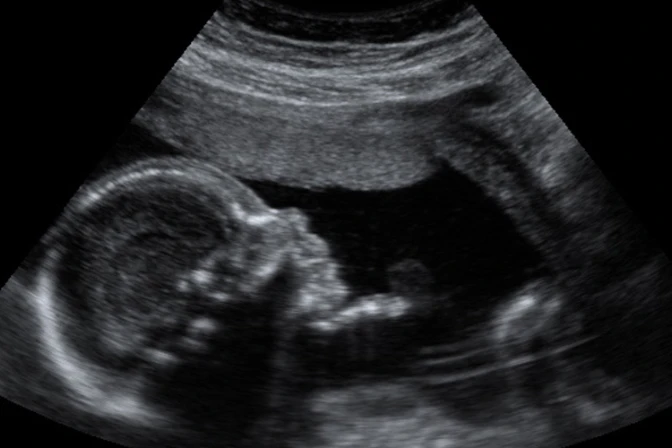

El término "hospice" perinatal hace referencia a la medicina fetal y a las curas paliativas prenatales, así como al acompañamiento del feto como paciente, incluso en las condiciones patológicas más extremadas.